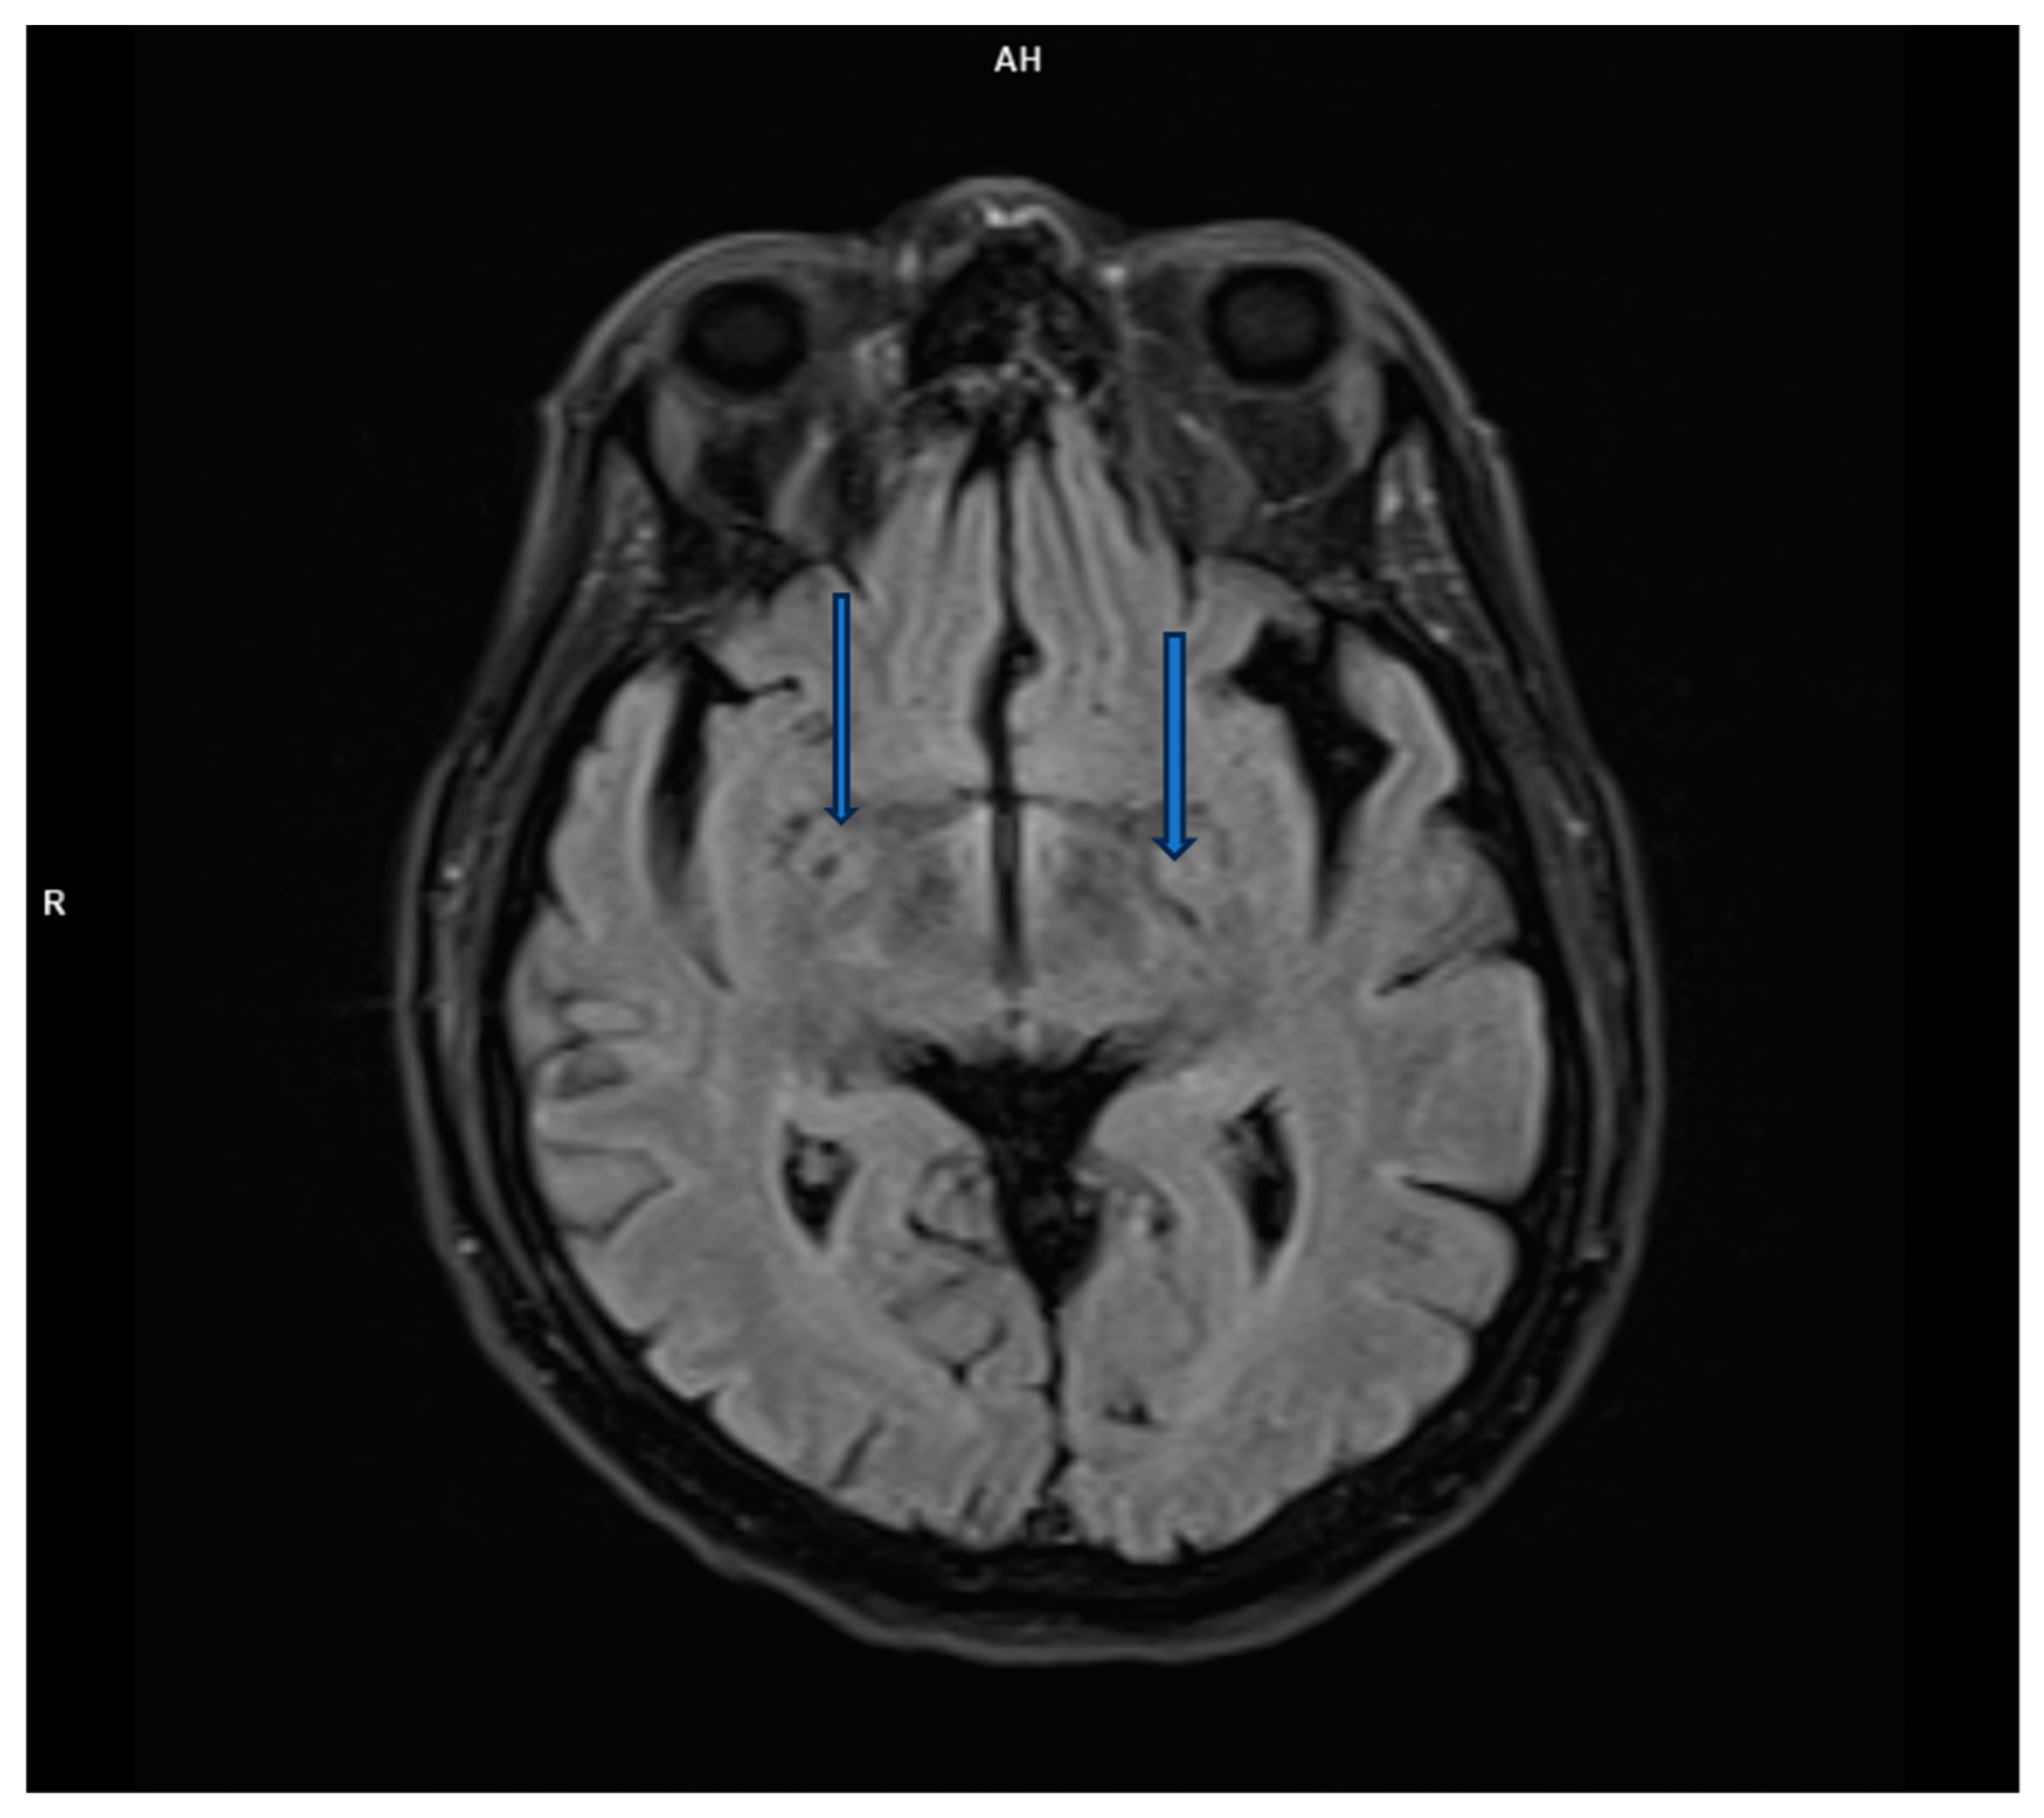

Magnetic resonance imaging (MRI) is a highly sensitive test (over 90%) for detecting herpes simplex encephalitis. Lesions appear hypodense on T1 and hyperintense on T2 and FLAIR, often affecting the temporal lobes, having progressed along the limbic system to the inferior frontal lobes and insular cortex. High-resolution FLAIR can reveal thalamic changes not visible on DWI, while the basal ganglia are usually unaffected. Immunocompromised patients may show atypical patterns outside the frontotemporal regions and often have widespread brain involvement, including the brainstem and cerebellum, but in one-third of patients, there are no pathological changes on MRI [8].

However, brain magnetic resonance imaging (MRI) revealed diffuse cortical atrophy with widened cerebrospinal fluid spaces and prominent perivascular spaces bilaterally in the subinsular region (Figure 1, Figure 2 and Figure 3).

Figure 3. T2-weighted transverse MRI scan reveals enlarged perivascular spaces.